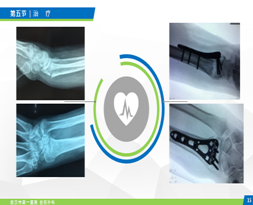

五、治疗